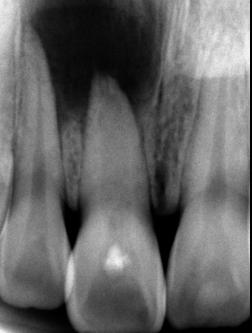

Las lesiones traumáticas de los dientes permanentes son comunes y afectan entre el 10.5% y el 17.3%. La extrusión, la luxación lateral y la intrusión se encuentran entre los tipos más graves de traumatismo dental que pueden alterar el suministro vascular a la pulpa. Radiográficamente, las partes apical y lateral del alvéolo parecen vacías y, en general, el espacio del ligamento periodontal está agrandado. La obliteración del canal pulpar (OCP) y la necrosis pulpar (NP) son las consecuencias más frecuentes de la luxación extrusiva, mientras que la reabsorción radicular (RR) es menos frecuente. Las complicaciones dependen de factores como la gravedad de la lesión, el estadio de desarrollo radicular y la presencia de una alta carga bacteriana bucal. Las complicaciones pulpares y periodontales son más frecuentes en dientes con raíces completamente formadas que en ápice abierto. La prevalencia de obliteración del canal pulpar (OCP) como consecuencia de lesiones por avulsión y luxación está entre el 3 y el 24%. Por el contrario, es muy poco probable que los dientes con ápice cerrado presenten revascularización y a menudo desarrollan

Figura 2. Imagen representativa de una luxación extrusiva en el órgano dental 11 que presenta un cambio de coloración en la encía.

necrosis pulpar. Las lesiones por luxación extrusiva requieren un tratamiento inmediato, consistente en reposicionamiento y estabilización. El tratamiento comienza con un correcto diagnóstico clínico y radiográfico, seguido del reposicionamiento manual del diente en el alvéolo y la colocación de una férula flexible, para permanecer in situ durante aproximadamente 2 semanas.6

Diagnóstico

El traumatismo de los tejidos de soporte (luxación extrusiva, luxación lateral, luxación intrusiva y avulsión dentaria) comprende del 15 al 61% de los episodios traumáticos y se consideran como las lesiones más graves. Las complicaciones relacionadas con este tipo de traumatismos pueden ocurrir semanas, meses e incluso años después del accidente traumático. La obliteración del canal pulpar, la necrosis pulpar y la reabsorción radicular se refieren a las secuelas más comunes, el peor pronóstico está relacionado con la reabsorción radicular. Estas complicaciones han mostrado valores de prevalencia que dependen de la gravedad de la lesión y del estadio de desarrollo radicular. La obliteración del canal pulpar después de una luxación y avulsión dental muestra una prevalencia de entre

el 3 y el 24%. Por otro lado, la necrosis pulpar puede ocurrir en el 64% y el 77% de las luxaciones extrusivas y laterales, respectivamente, y para las luxaciones intrusivas y avulsiones dentarias este valor puede llegar al 100%. También se ha demostrado que la prevalencia de la reabsorción radicular después de luxaciones y avulsiones varía mucho. En las reimplantaciones dentales, el periodo extraalveolar y el medio de almacenamiento son aspectos cruciales en el desarrollo de este tipo de secuela. Algunos estudios han revelado que la reabsorción inflamatoria ocurre entre el 5 y el 70% de las luxaciones y entre el 20 y el 50% de las avulsiones. De igual forma, la reabsorción de reposición se ha demostrado que es más frecuente en la luxación intrusiva, con una prevalencia del 20 al 40%, y en la reimplantación dentaria esta secuela ocurre en el 50 al 70% de los casos.7

Entre todas las lesiones orofaciales, las lesiones dentales traumáticas (TDI) son una de las más prevalentes. Representa el 18% de todas las lesiones en niños de 0 a 6 años (Figura 2) y Las lesiones por luxación se pueden clasificar en varios tipos según el grado de desplazamiento: conmoción cerebral, subluxación, luxación lateral, extrusión y avulsión. La raíz del germen del diente temporal y del permanente se encuentran muy cerca, por lo que las complicaciones a largo plazo de las TDL, como la infección de los dientes temporales, también pueden dañar los dientes sucesores en desarrollo. La prevalencia de lesiones por luxación es alta entre los niños pequeños debido a la naturaleza resistente de su hueso alveolar y sus estructuras de soporte (Figura 3). Se ha informado que las lesiones por intrusión causan más alteraciones de la mineralización en

los dientes sucesores en comparación con otros subtipos de lesiones por luxación.8

Después de lesiones traumáticas graves, como luxación extrusiva y avulsión, el diente no solo queda sujeto a un daño tisular extenso, como la ruptura completa del suministro neurovascular, sino que también puede quedar expuesto a contaminación externa y bacterias a través de diferentes vías.9

Estas lesiones pueden afectar directa o indirectamente la vida de las personas, cambiando su apariencia, habla y posición de los dientes. Las TDI en niños y adolescentes se consideran problemas de salud graves en todo el mundo. Para los niños de 0 a 6 años, las lesiones bucales representan el 18% de todas las lesiones físicas, y la boca es la segunda área del cuerpo afectada más común. Un metaanálisis reciente realizado por Petti et al. sobre lesiones dentales traumáticas informaron una tasa del 7% que afectan a los dientes temporales en todo el mundo, con frecuente recurrencia del trauma.10

Debido a la lesión del ligamento periodontal, el diente luxado debe reposicionarse con cuidado lo antes posible. Según las guías actuales, un

3. Radiografía periapical de una luxación extrusiva en el órgano dental 11

Trauma en niños y adolescentes: luxaciones

Figura